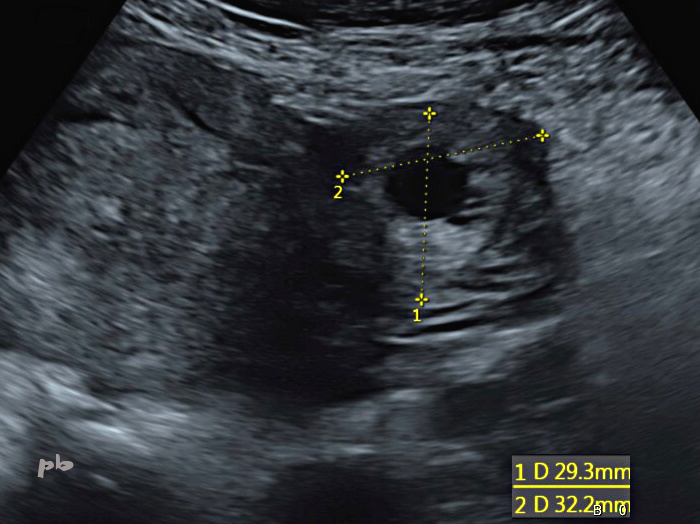

18- GEU droite

Sac gestationnel (croix 2) vu dans la trompe droite.

Cette dernière, mesurée à 10,4 mm, est soulignée par un peu de liquide.

18- Right ectopic pregnancy

Gestational sac (cross 2) seen in the right tube.

The latter, measuring 10.4 mm, is outlined by a small amount of fluid.